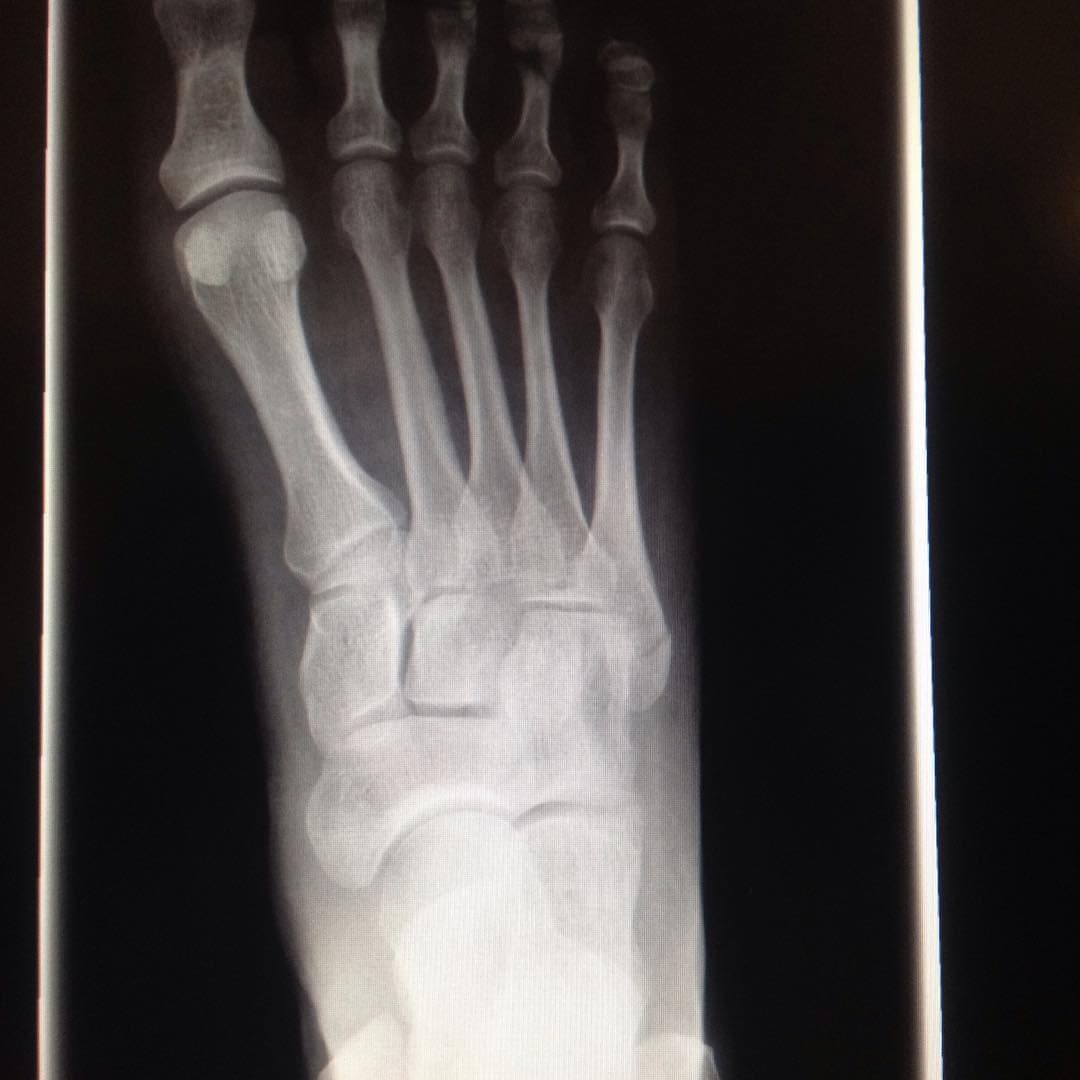

Bones, one of them broken.